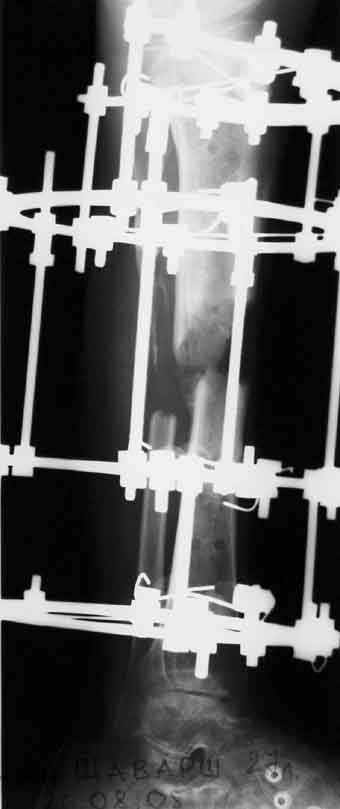

1 июня произведено удаление гвоздя, дренаж костномозгового канала, остеосинтез аппаратом Илизарова ( after 1; 2).

Ввиду относительной тугоподвижности ложного сустава и наличия признаков репаративной активности костной ткани рентгенологически, после 10 дней компрессии на стыке отломков, начали дистракцию по 1мм в день. Выписан на амбулаторное лечение. Отделяемое в нижней трети голени прекратилось, ранка закрылась. Интраоперационно и 5 дней после операции получал ципроксациллин. В июле по передней поверхности голени в зоне регенерата открылась ранка с обильным гнойным отделяемым. После локального лечения, ранка в течении двух недель эпителизировалась и полностью закрылась. Дистракцию не прекращали. (during 1, 2)